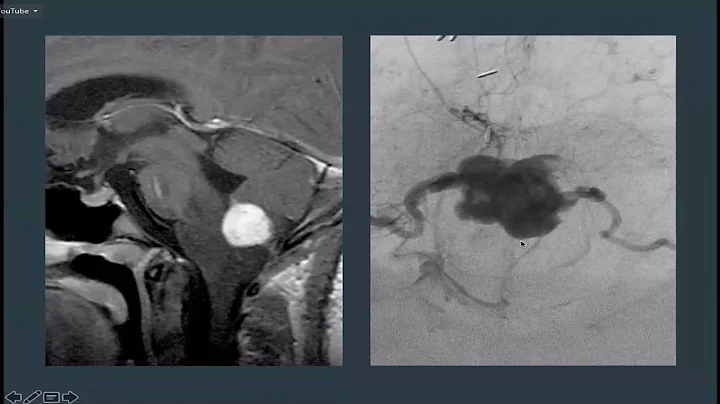

manifestaciones del von hipple lindau oncolog...

... of blockage of the endolymphatic duct sac with high drops or hemor...